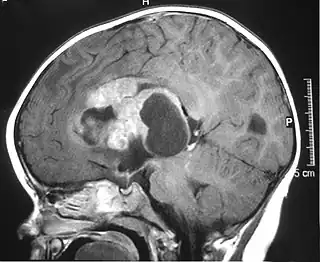

Imagen de resonancia magnética de un tumor teratoideo/rabdoide atípico (ATRT) supratentorial en un niño. | ||

Los tumores rabdoides se dividen en tres según su localización inicial: renal, extrarrenal y del sistema nervioso central, este último se denomina tumor rabdoide teratoide atípico del sistema nervioso central y representa entre el 1 y el 2% de los tumores cerebrales en niños de menos de 3 años.